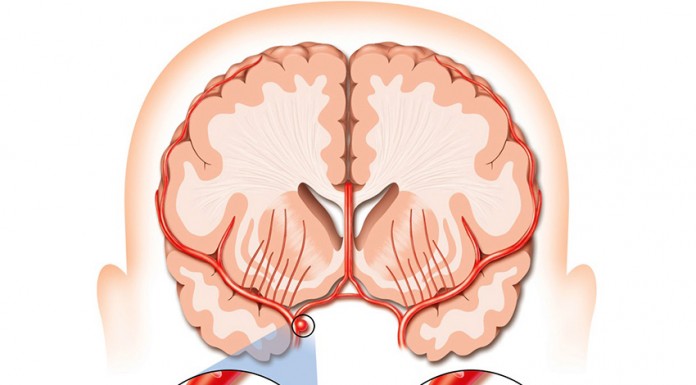

Mais e melhor prevenção, consolidação da rede de Unidades de AVC e melhores tratamentos e um encaminhamento mais célere através da via verde são...